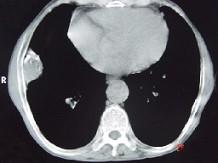

CT图像如下,最可能诊断为 ( )A、膈膨升B、纵隔肿块C、右侧胸膜良性病变D、肋骨病变侵犯胸壁E、右肺肺占位

问题 CT图像如下,最可能诊断为 ( )

选项 A、膈膨升 B、纵隔肿块 C、右侧胸膜良性病变 D、肋骨病变侵犯胸壁 E、右肺肺占位

答案 C